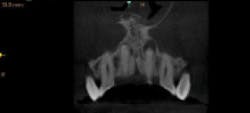

Figures 4–8: Apical lesion on tooth No. 9 is confirmed on all 3-D views

I examined a patient who had experienced trauma to his two front teeth approximately five years prior and was now experiencing occasional pain. From an x-ray, the problem could not be diagnosed as definitive (figure 3). However, as soon as I took the 3-D image, I could see an abscess, which required a root canal (figures 4–8).